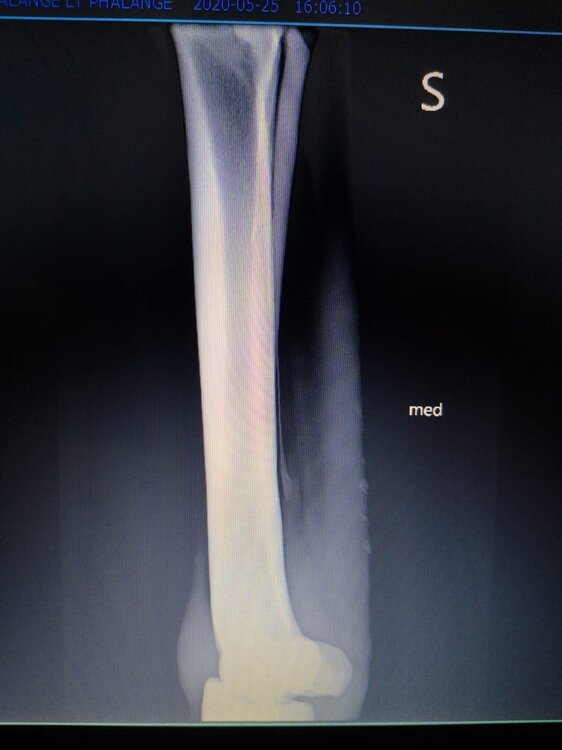

Salve volevo chiedervi qualche informazione in merce tò a un problema che ho avuto con la mia puledra. Qualche settimana fa mentre stavo lavorando alla corda è scivolata urtato l'arto posteriore sinistro. Arrivati in box ho messo dell'acqua a pressione perché si era gonfiato sia il nodello sia il pastorale. Già l'indomani l'arto era sgonfio ritornato normale, quindi ho continuato a lavorarla. Ma dopo qualche giorno di lavoro alla corda leggerissimo, al rientro in box ho notato che sia il nodello che il posturale gonfiavano nuovamente. Allora ho chiamato il veterinario che ha detto che la cavalla aveva una lussazione e mi ha insegnato come cura una fasciatura con della creta per 24h per cinque giorni e un antinfiammatorio. Dopo un paio di giorni la fasciatura ha fatto come delle vesciche e il gonfiore è aumentato dal pastorale alla garra. Abbiamo chiamato un altro veterinario abbiamo fatto vedere anche a lui la cavalla e diceva che poteva essere la frattura del ditino, ma si dovevano fare le lastre per essere sicuri. Ora abbiamo fatto le lastre e il radiologo dice che c'è dell'infiammazione ma non c'è niente di grave. Il veterinario,viste le lastre dice che deve essere operata. Allora abbiamo consultato un'altro veterinario che dice che la cavalla non ha assolutamente niente. Ora io vi allego le radiografie, datemi un vostro parere perché non só più cosa fare. Grazie